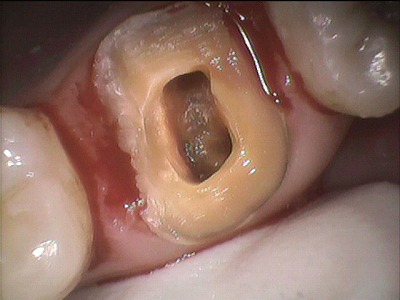

かぶせ物を外したところです。

さて

中をキレイにお掃除していきます。

お隣の歯と歯との隙間が虫歯になっており

さらに歯茎が腫れています。

フロスを毎日してるけど

隙間はなかなかとりきれなかったようです。

しかも奥歯は磨きにくい!!

バイキンがたまると

歯茎は腫れ炎症をおこしてしまいます。

4つめの歯の根っこがみつかったそうです。

歯の根っこを探る器具です。

歯の根っこ中をきれいにしていきます。

そして、この穴に

特殊なお薬を入れ込み仮の蓋をします。

仮の蓋をしてから最低3日から1週間

お薬を浸透させるべく

仮の蓋状態です。

昨日はここまで。

時間にして約1時間。

ここまでが、

歯科金属を除去し、根っこの殺菌処理、仮の蓋編

です。

1週間ほどして

仮の蓋をあけ、

何度かお薬の詰め替えをし

完全にきれいな状態になるまで

繰り返します。

結構手間隙かかります。